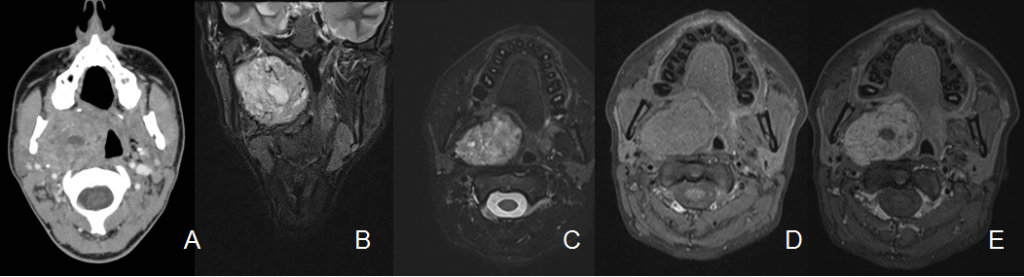

A. Tc de cuello con contraste. B. RM STIR coronal. C. RX T2 fat sat axial. D y E. RM T1 fat sat sin y con contraste i.v.

Masa bien delimitada de contornos lobulados localizada en el espacio parafaríngeo preestíleo derecho: medial a la cara interna del músculo pterigoideo medial (flechas verdes) y anterior a la apófisis estiloides (flecha negra) que se encuentra desplazada posteriormente. La masa es heterogénea por la presencia de áreas de degeneración necróticoquística (asterisco). Presenta una cápsula hipointensa en secuencias potenciadas en T2 (flecha amarilla). Tras la administración de contraste se realza de forma moderada.